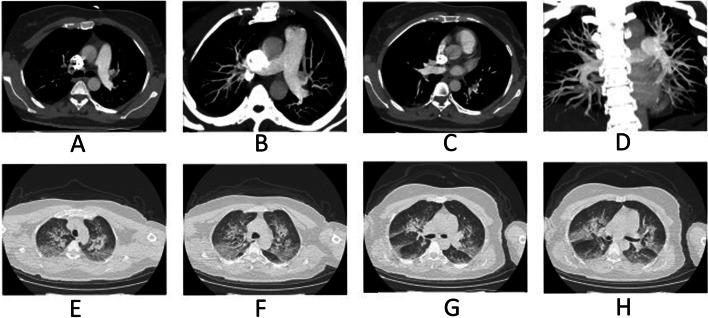

Fig. 2.

High altitude pulmonary edema (HAPE) in a 39-year-old boy who had dyspnea at rest and worsening cough for 3 days before admission. A-D Axial image of CT pulmonary angiogram showing thrombi as filling defects in right main pulmonary artery extending into its branch and in distal left pulmonary artery with extension into its superior branch. E-H Multiple lesions of ground glass opacity, patchy lesions and partial consolidation in the CT imaging were presented in the bilateral lung center along the bronchovascular bundle